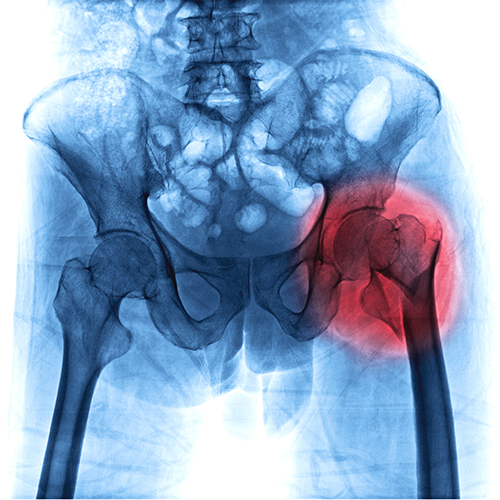

Relief For Radiating Hip Pain

Hip pain is typically caused by injury or strain to the joint or surrounding soft tissue. Pain inside your hip or groin area is a common complaint and is consistent with a joint issue. Pain on the outer aspect of your hip, in your upper thigh, or buttock region, is likely due to a problem with the muscles or soft tissues surrounding the hip joint.

Having a limited range of motion in the hips often alters movement and mechanics throughout the lower extremities. Pain and weakness can further reduce the range of motion and change the way you walk.

Some common causes of hip pain include:

- Bursitis

- Tendon or muscle strain

- Rheumatoid arthritis

- Hip fractures (common with age, but can also be the result of a fall)

- Tendinitis

Getting relief from hip pain doesn’t necessarily involve the use of heavy drugs such as opiates or surgery. Physiotherapy can improve your joint function while also easing your pain and stiffness.